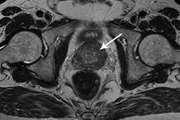

MRI in prostate cancer(Review)

Imaging studies play an important role in detection and management of prostate cancer and MRI especially with the use of endorectal coil because of high contrast resolution is recognized as the best imaging modality in evaluation of prostate cancer